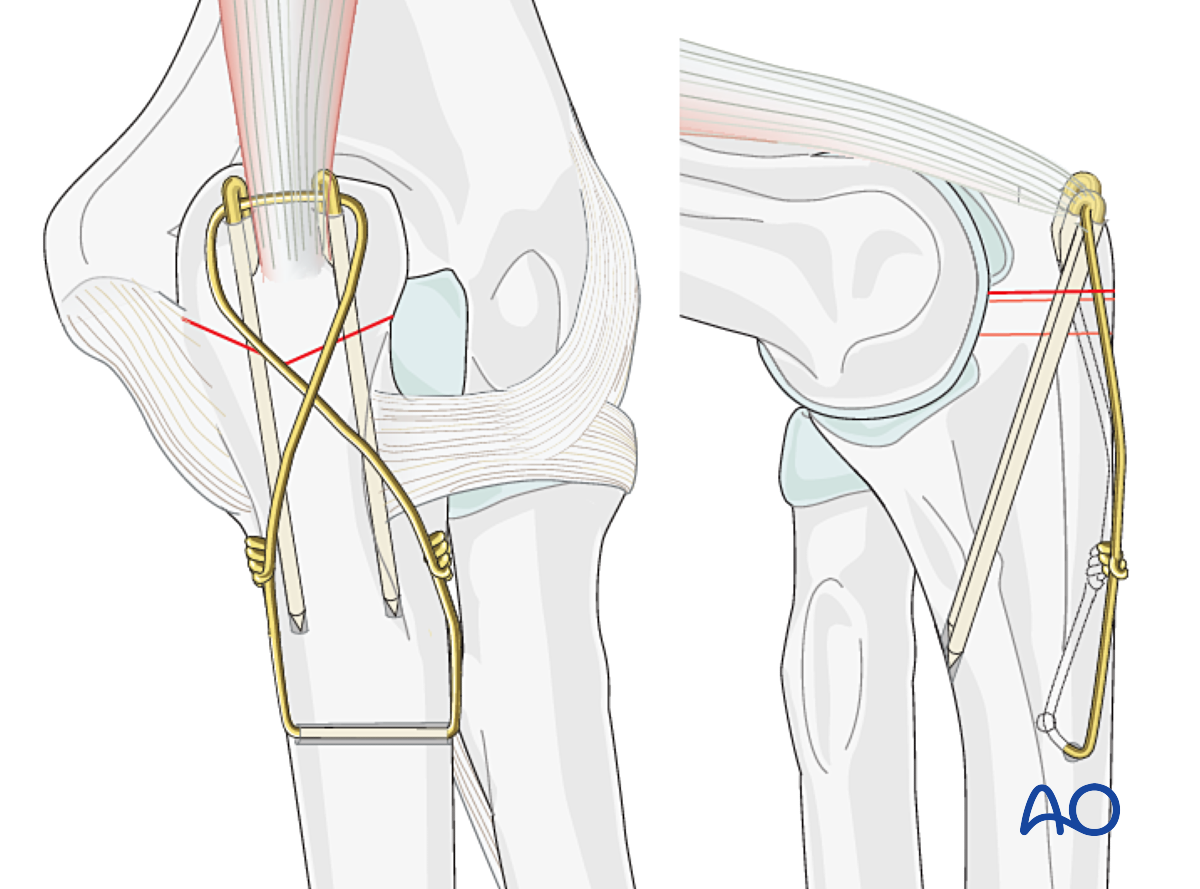

Остеосинтез коленного сустава

Остеосинтез коленного сустава 103 фотографий